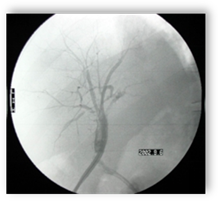

内镜诊疗技术在肝胆疾病的应用:采用国际先进的内窥镜系统,PTCD或PTBD结合ERCP或ENBD技术、金属覆膜支架的使用治疗肝移植术后或普通患者的肝胆管结石、胆道狭窄以及恶性肿瘤患者的胆道瘤栓消融再通手术。